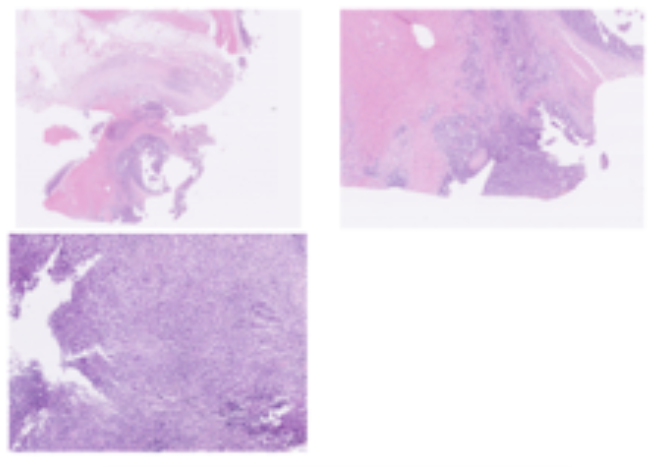

탐색적 개복술을 진행한 결과, 소장에서 종괴(덩어리)가 확인되었습니다.

이 종괴로 인해 장이 좁아지면서 여러 이물이 걸려 있었고, 그로 인해 장에 구멍이 생긴 상태였습니다.

소장 종괴와 주변 림프절을 조직검사한 결과, 소장 선암종으로 확인되었습니다.

이는 소장 부위에서 잘 발생하는 악성 종양으로, 다른 장기로 전이되거나 침습할 가능성이 높은 종양입니다.